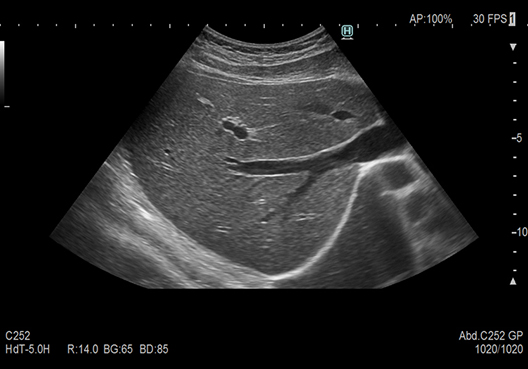

Micro convex transducer (Single crystal) delivering high image quality and easy application in routine examinations. The transducer shape, as well as the performance of the piezoelectric element and heat dissipation structure, have been optimized to achieve both image quality equivalent to a conventional convex transducer, and low-stress operability. In addition, it seamlessly supports examinations in various scenes from diagnoses to treatments.

Transmission and reception technology to achieve clarity of imaging from near to far field. Reduced focus dependency and patient dependency.

[eFocusing] Focused at All Depths